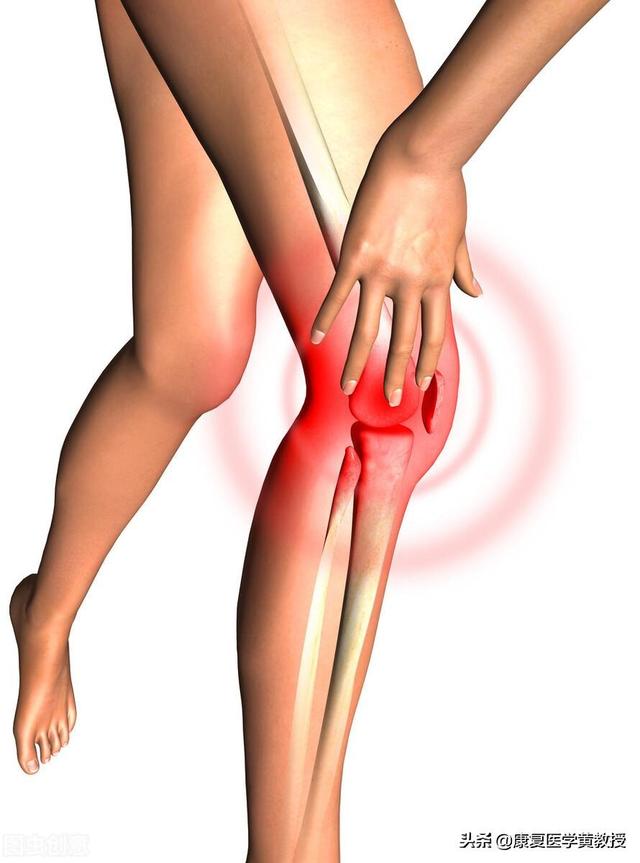

Les patients souffrant d'arthrose à un stade précoce présentent souventTension derrière le genou.auraitFaiblesse des articulationssurtout s'il y auralit. battre ses jambes faiblesLa manifestation de la maladie, chez certains patients qui s'accroupissent, se traduit par des craquements évidents des articulations et s'accompagne de douleurs. Au fur et à mesure que la maladie s'aggrave, les symptômes du patient deviennent plus sévères, et certains patients présentent peu à peu des symptômes d'arthrose.Douleur dans les articulations lors de la montée et de la descente des escaliers et lors de la marche sur terrain plat.Dans les cas les plus graves, les patients peuvent présenter des douleurs articulaires même au repos, avec desTroubles de la mobilité articulaire et déformations des articulations。

Pour l'arthrose de l'articulation du genou, il est recommandé aux femmes de proposer une radiographie de l'articulation du genou ou un examen magnétique de l'articulation du genou afin de préciser l'état du cartilage de la cavité articulaire et l'importance de l'ostéophyte qui se forme à la fin. Cela peut aider les patients à suivre un traitement scientifique.